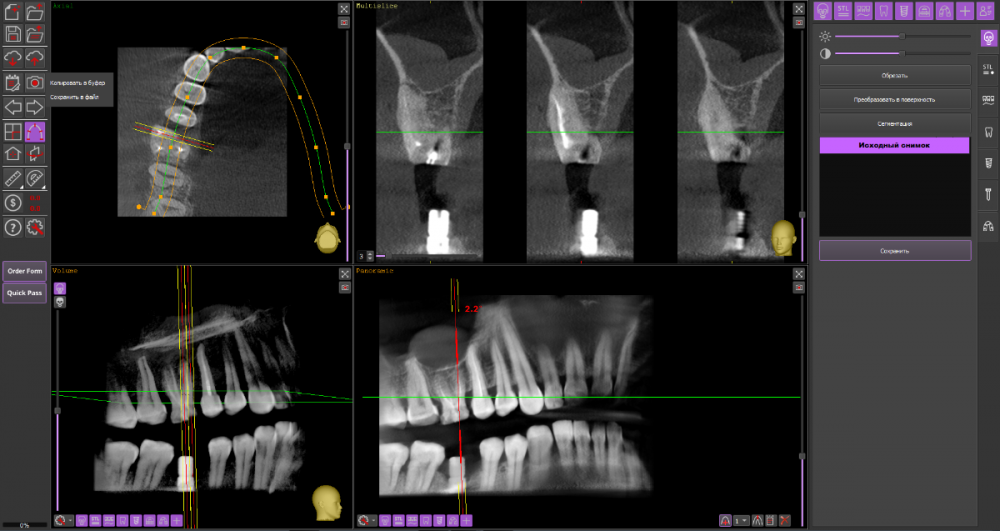

Алексей82 Опубликовано 10 марта, 2022 Автор Поделиться Опубликовано 10 марта, 2022 Здравствуйте. Вот ссылка на КТ. Посмотрите пожалуйста. Или может надо было скрин сделать чегото. https://dropmefiles.com/zxr3f Ссылка на комментарий

wladdX Опубликовано 10 марта, 2022 Поделиться Опубликовано 10 марта, 2022 (изменено) Попробовать поработать в корневых каналах можно, насколько это будет успешно, сказать невозможно. Изменено 10 марта, 2022 пользователем wladdX 1 1 Ссылка на комментарий